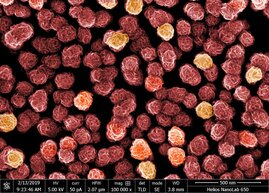

Die Nanomedizin macht Fortschritte. Doch die winzigen Nanopartikel, die als Träger für

Medikamente erforscht werden, könnten in Zukunft ihren Weg in…